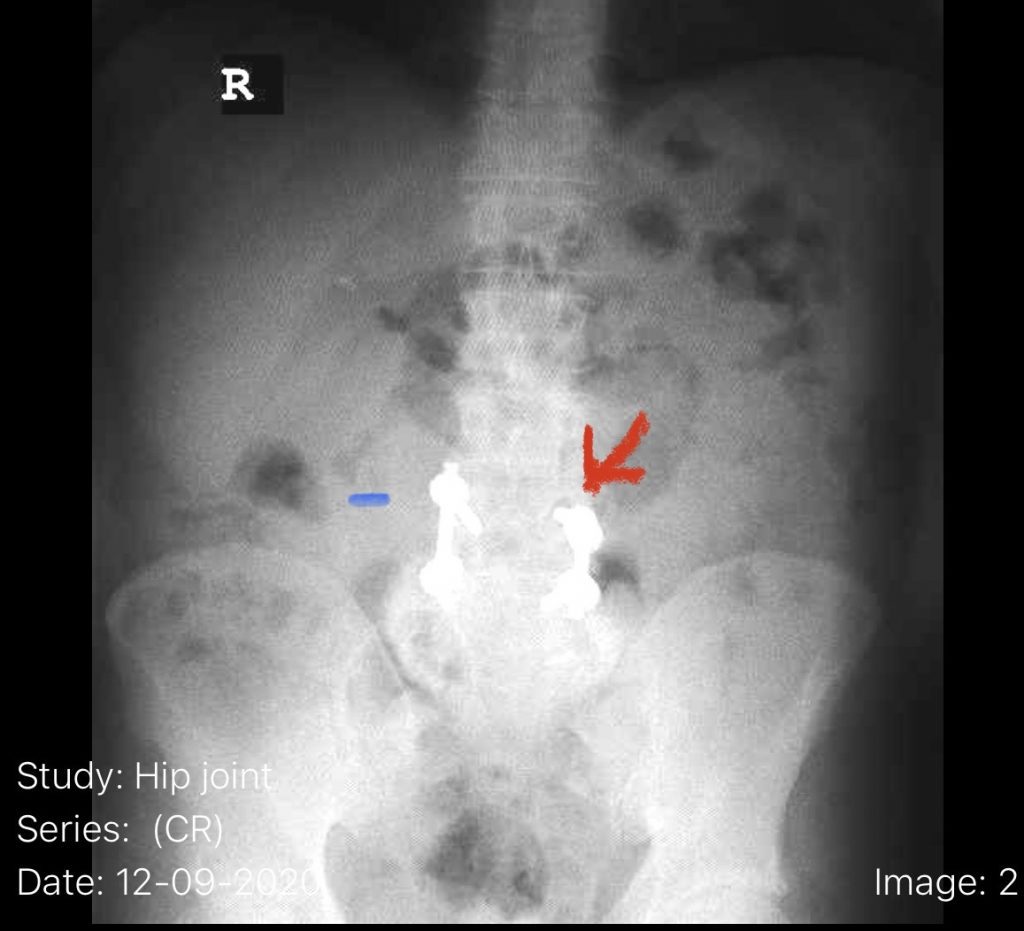

The patient also had a retrolisthesis at L3-4 with mild stenosis. It was also noted that he had lucencies around the L4 screws, suggesting a pseudoarthrosis at L4-5. which is a lack of bony fusion (Fig 6). Patient was had failed conservative management and was taken to the operating room where his construct was explored. There was a complete lack of bony fusion mass between L4 and L5 and the screws were loose. Interestingly the L5-S1 region had a solid bony fusion where we had used BMP, but the L4-5 region did not. We removed the construct and removed the remnant of L4 lamina and the inferior processes and decompressed from L3 to to L5, decompressing well the L4 and L5 nerve roots. We placed new instrumentation from L3-5 with the use of BMP which was discussed with the patient prior to surgery (Fig 7). We also felt it was necessary because of the failure of the fusion. Post operatively the patient had an uneventful course with significant improvement of his prior symptoms.

Fig 7: Intraoperative fluoroscopic AP image of the new construct from L3-5. Note the very large lucency around prior L4 screw